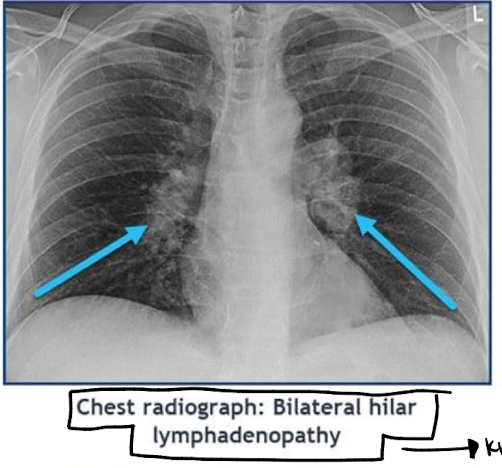

o Bilateral hilar adenopathy (CLASSIC FINDING)

o Imaging: bilateral hilar adenopathy

o Lofgren syndrome: erythema nodosum, bilateral hilar adenopathy, febrile polyarthralgia’s (joint pain plus fever)